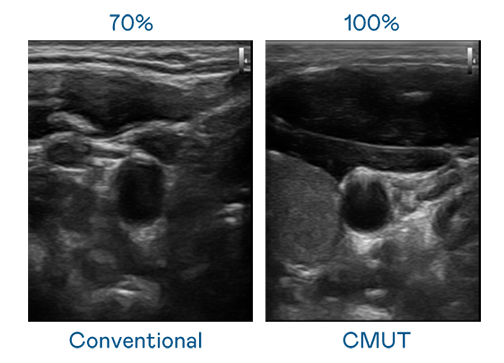

CMUT 技術是一種用電容式微機電元件來產生超音波訊號的技術。與傳統 PZT 壓電式技術相比,CMUT 頻寬增加 30%,更寬頻的超音波訊號讓影像解析度大幅提升,是實現高影像品質醫療超音波掃描、促進精準醫療發展的關鍵技術。

大頻寬帶來超清晰影像

超音波影像的解析度高低,首先取決於探頭能發出的訊號頻寬。91nba高清免费观看 CMUT 可提供高清晰的超音波訊號,提供高頻寬、高靈敏度、影像紋理細節更高的超音波影像,協助醫護人員縮短影像判讀時間及利用精準的醫療影像進行診斷。